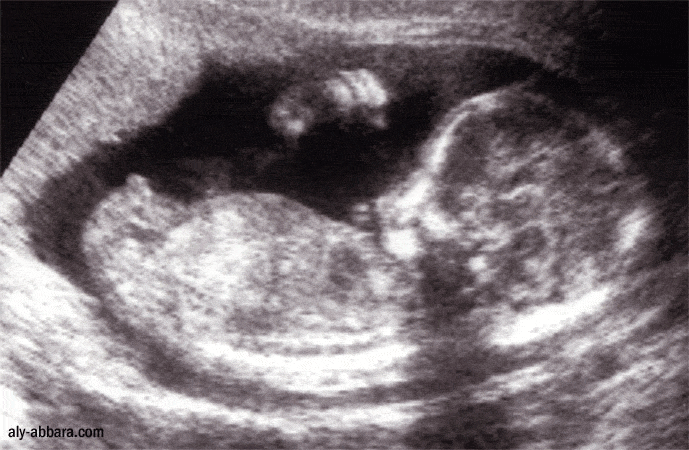

Mon calendrier de grossesse la 15ème semaine de grossesse (17 SA) 4ème mois Le premier mouvement ressenti est variable d'une femme à La 15e semaine de grossesse correspond à 17 semaines d'aménorrhée (SA) Notre corps continue à changer et on est maintenant très à l'étroit dans nos vêtements La croissance de notre bébé se poursuit, elle aussi, tout doucement © Eraxion Sommaire Côté bébé Le développement du bébé pendant la semaine 15 de grossesseSunt o gravidutza in 13 sapt si 5 zile si deja de cateva zile simt usoare miscari are lui bebeAm fost mirata pentru ca la prima sarcina am simtit miscari la 1718 saptamaniMama mia spus ca nu am cum sa simt miscari atat de devreme dar eu sunt absolut sigura este exact in dreptul uterului si am simtit exact ca la prima sarcina,un